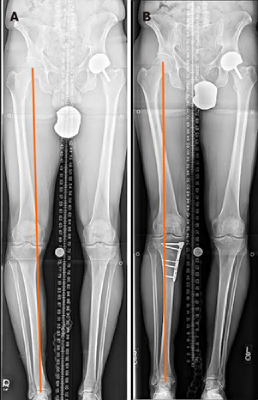

Knee preservation involves the use of non-surgical or surgical methods to maintain the integrity of a deteriorating joint. Its goal is to delay or prevent the need for joint replacement surgery, thus preserving natural joint function and mobility.